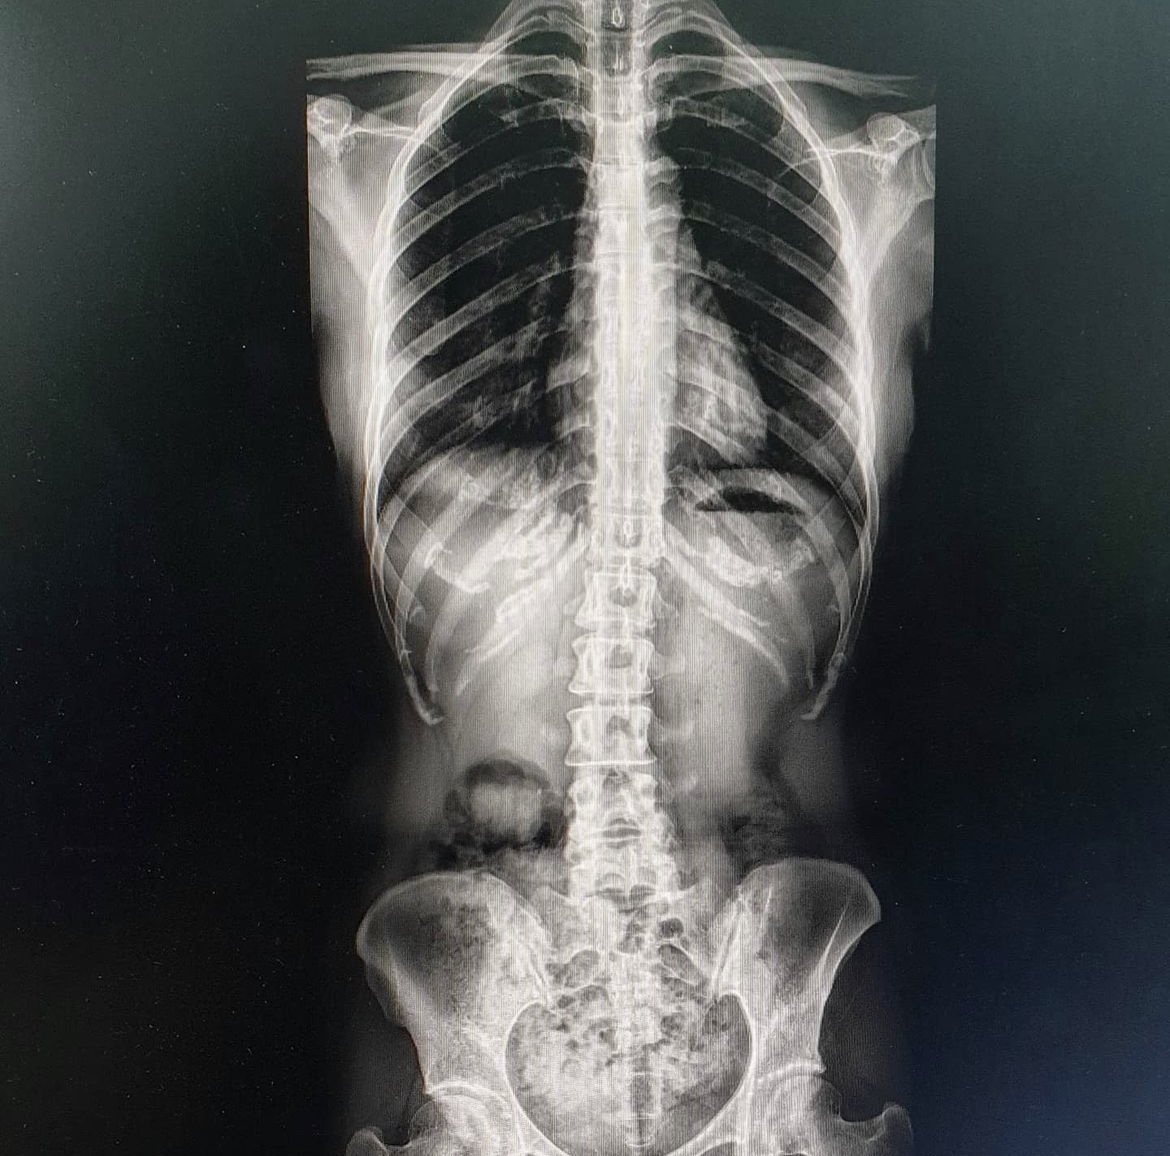

그런데 10년 넘게 안좋은 자세로 일한 것이 결국 허리에도 문제를 일으켰습니다. 척추가 위쪽에 한 번, 아래쪽에 한 번 휘는 측만증이라는 진단과 함께 허리디스크 판정.